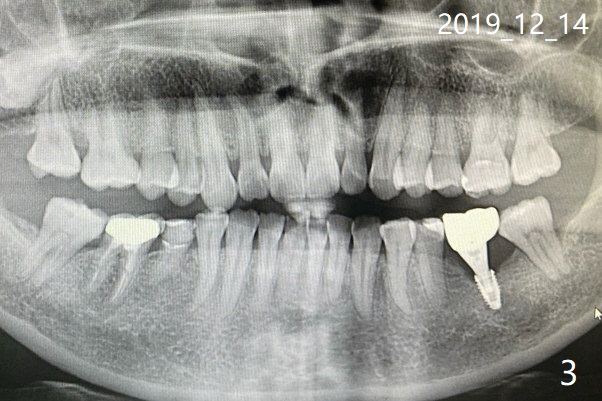

这边我找到有Neo种植体的诊所了,可那医生说应该植骨,重种。您能把我在美国时刚做完植体和装上牙冠后的x片发给我吗?我也把12月1号,8号和14号的x片发给您(图三至五). 另外,植体里的螺丝会磨没了吗? December 14, 2019, 3:21:23 AM EST